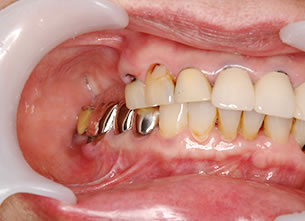

症例1 : 上下顎無菌顎症例

69歳、男性。

• 上顎は両側サイナスリフトと同時に即時荷重を行った。

• 下顎は抜歯即時埋入即時荷重を行った。

• 最終補綴物は、チタンのP.I.B.とM.B.のコンビネーションで修復した。

• 本症例の要旨は第39回日本口腔インプラント学会(大阪)にて症例報告した。